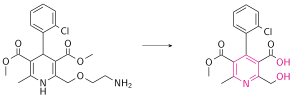

| Metabolites | Various inactive pyrimidine metabolites |

Amlodipine has been studied in healthy volunteers following oral administration of 14C-labelled drug.[53] Amlodipine is well absorbed by the oral route with a mean oral bioavailability around 60%; the half-life of amlodipine is about 30 h to 50 h, and steady-state plasma concentrations are achieved after 7 to 8 days of daily dosing.[7] In the blood it has high plasma protein binding of 97.5%.[43] Its long half-life and high bioavailability are largely in part of its high pKa (8.6); it is ionized at physiological pH, and thus can strongly attract proteins.[7] It is slowly metabolized in the liver by CYP3A4, with its amine group being oxidized and its side ester chain being hydrolyzed, resulting in an inactive pyridine metabolite.[54] Renal elimination is the major route of excretion with about 60% of an administered dose recovered in urine, largely as inactive pyridine metabolites. However, renal impairment does not significantly influence amlodipine elimination.[55] 20-25% of the drug is excreted in the faeces.[56]